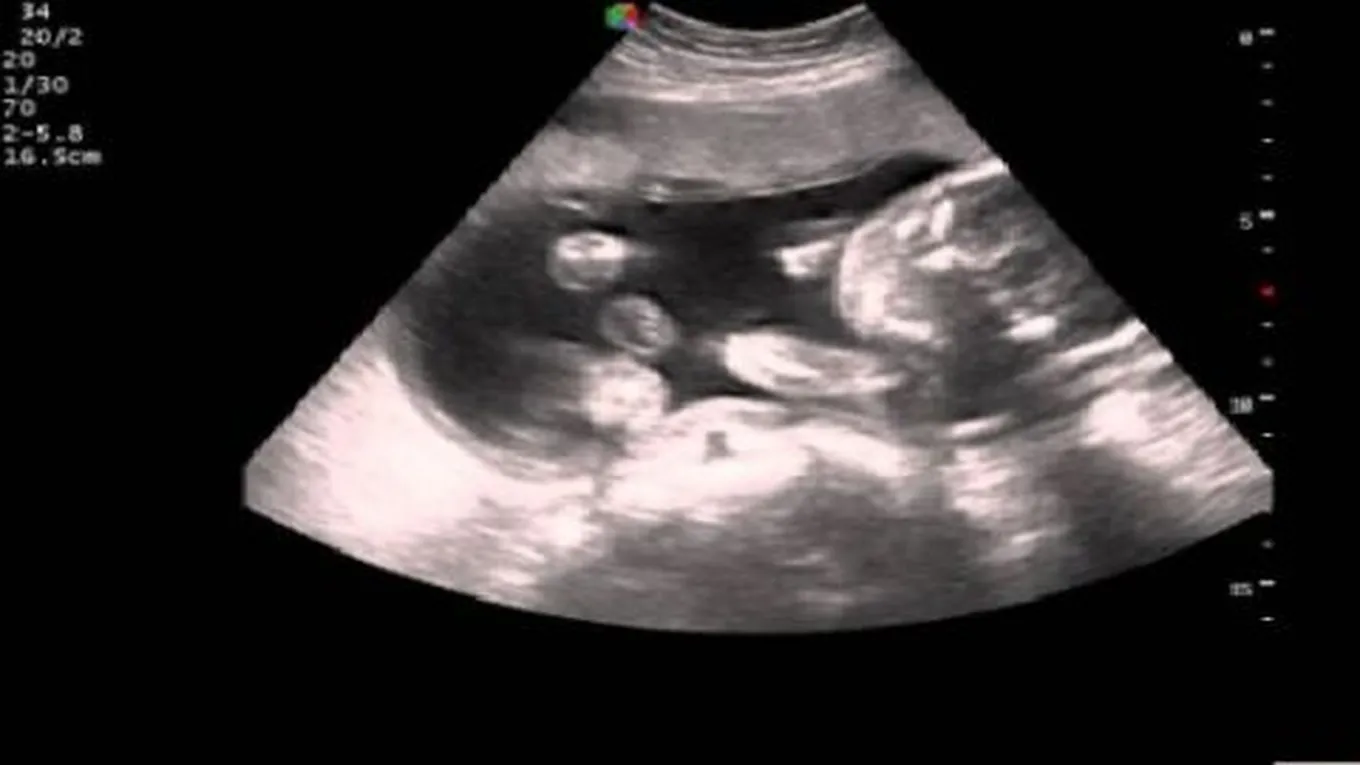

يمكن عمل فحوصات خاصة أثناء الحمل (بالإنجليزية: Prenatal testing) للكشف عن ما إذا كان هنالك تغيرات غير طبيعية في جينات الجنين، حيث يتم عمل هذه الفحوصات إذا كان هناك شكوك بأنّ الطفل سيعاني من اضطراب وراثي أو كروموسومي، وبالرغم من أنّ مثل هذه الفحوصات تساعد على اتخاذ قرارات حاسمة تتعلق بالحمل، إلا أنّه لا يمكن تحديد جميع المشكلات الوراثية والعيوب الخلقية المحتملة،[1] ويتم إجراء الاختبارات الجينية (بالإنجليزية: Genetic tests) عن طريق تحليل عينات صغيرة من الدم، أو من أنسجة الجسم، وهي تحدد ما إذا كان إحدى الأبوين أو الجنين يحمل الجينات لبعض الاضطرابات الوراثية.[2]

تقسم الاختبارات الجينية السابقة للولادة إلى اختبارات الفحص (بالإنجليزية: screening tests)، والتي تبين ما إذا كان الجنين أكثر عرضه للإصابة بمرض معين أو لا، لكن لا يمكن تأكيد ذلك، واختبارات التشخيص (بالإنجليزية: diagnostic tests) والتي تعطي نتيجة أكثر دقة، وعادة ما تجرى اختبارات التشخيص بعد أن تعطي اختبارات الفحص نتائج إيجابية،[3] ومن أهم أنواع اختبارات التشخيص ما يلي:[2]

يسمى هذا الإختبار باختبار الغشاء الداخلي المحيط بالجنين، وهذا الغشاء يطلق عليه طبياً مسطلح بَزْلُ السَّلَى (بالإنجليزية: Amniocentesis)، وهو اختبار يتم إجراؤه عادة بين الأسبوعين 15 و20 من الحمل، يقوم الطبيب بإدخال إبرة مجوفة في الرحم لسحب كمية صغيرة من السائل الأمنيوسي المحيط بالجنين، حيث يمكن اختبار هذا السائل لتشخيص الامراض الوراثية عند الجنين وتحديد جنس الطفل، كما يستخدم عندما يكون هناك خطر الولادة المبكرة لمعرفة مدى نضج رئتي الطفل، لكنه قد يزيد هذا الاختبار من خطر حدوث الإجهاض.[2]